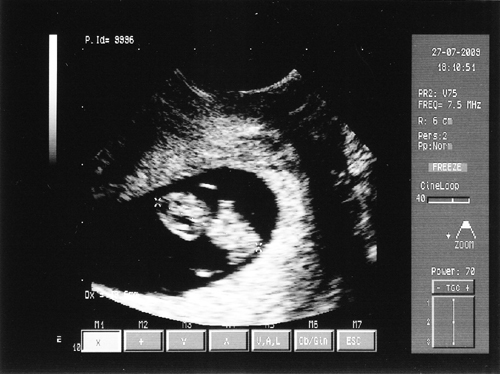

Íme egy kis meglepetés!!!

Kép Babócánk 19 mm! :D

Ma voltam a saját dokimnál ellenőrzésen, megbeszéltük, hogy mik a teendők a továbbiakban, vérvétel, védőnő stb.

Ha már ott voltam azt mondta, nézzük meg a babát, kíváncsi rá.

Azt mondta, minden rendben, a babóca 19 mm, a szívecskéje szépen dobogott, a köldökzsinórban látni lehetett a vér áramlását.

Olyan csodálatos ez az egész!!!!!!!!!!!!!!!!!! Nagyon, nagyon, nagyon ... boldog vagyok!!!!!!!!!!!!!!!!!!! :D :D :D :D :D :D :D :D :D